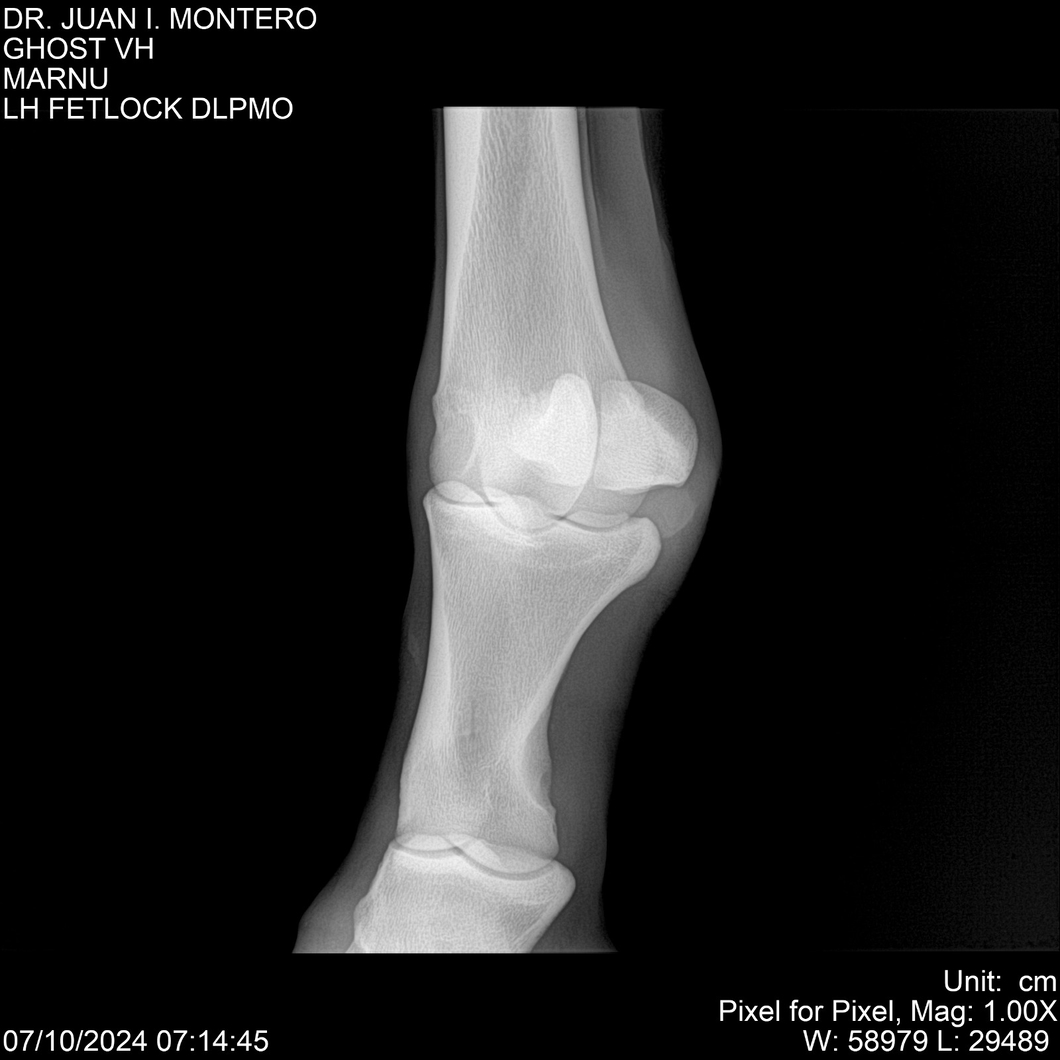

LOTE 15, GHOST VH 🔥 🔥 🔥 Lote Anterior Volver al remate Lote Siguiente Ficha Contacto Montevideo - Ficha del Lote Identificador: #282525 Categoría: Yeguarizos Montevideo - 69 Visualizaciones ClicData Contacto Empresa: Abelenda N. R., Walter Hugo Nombre*: Teléfono* : E-mail* : Mensaje Enviar Registrese gratis Este contenido Exclusivo está disponible sólo para usuarios registrados Ingresar